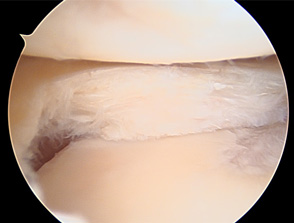

• 画像:正常な半月板関節鏡画像(内側)

正常な半月板関節鏡画像(内側)

• 画像:正常な半月板関節鏡画像(外側)

正常な半月板関節鏡画像(外側)

• 画像:損傷後内側半月板関節鏡画像

損傷後内側半月板関節鏡画像

• 画像:部分切除後内側半月板関節鏡画像

部分切除後内側半月板関節鏡画像